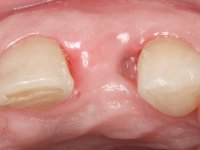

Paciente do sexo feminino, com 47 anos não fumadora. Apresentou-se na consulta com o dente 1.3 com tratamento endodôntico e com um espigão falso coto fundido, reabilitado com uma coroa provisória. Os dois incisivos laterais superiores são conoides e de reduzida dimensão. O dente 2.2 apresenta mobilidade, consentânea com uma significativa reabsorção óssea entre o dente 2.1 e o dente 2.3 Os dois incisivos centrais estão separados por um diastema de 3mm e o dente 2.3 apresenta uma oclusão cruzada com o dente antagonista. Verifica-se também a ausência de alguns dentes posteriores e uma higiene oral razoável. Na segunda intervenção realizada passados 8 anos, verificou-se que os incisivos centrais superiores se apresentavam cromaticamente mais escuros e apresentavam um sulco longitudinal no esmalte que estando pigmentado comprometia esteticamente o sorriso. O trabalho realizado na primeira fase do tratamento mostrava-se competente estética e funcionalmente. Por fim, um ano após a última intervenção, a paciente apresentou-se com uma fratura da faceta colocada no dente 2.1 provavelmente em resultado de estar em contacto com o coto do implante. A rigidez da anquilose implantar, pode ter sido a causa desta fratura. Outros casos deste tipo de fratura já foram observados por mim em situações clínicas idênticas. A faceta do dente 1.2 apresentava-se esteticamente comprometida e a própria estrutura dentária apresentava uma pequena cárie e, pelo que se recomendaria a sua substituição.

• Tratamento ortodôntico para fechar diastema entre os dentes incisivos centrais superiores e fazer a tração lenta do dente 2.2.

• Colocação de um Implante no local do dente 2.2. Reabilitação do implante com um “abutment” de componente coronário e gengival. em que o orifício de acesso ao parafuso fosse “camuflado” com uma faceta feldspática.

O tratamento iniciou-se com a re -preparação do coto do espigão falso coto fundido, com o objetivo de colocar as linhas de acabamento cervical com uma localização intra-sulcular e simultaneamente confecionar uma coroa provisória adaptada. Com um tratamento ortodôntico muito simples, fechou-se o diastema entre os incisivos centrais superiores e estabilizou-se esta posição com um arame colocado na superfície palatina dos centrais, funcionando como contenção. Posteriormente procurou-se fazer uma tração ortodôntica lenta do dente 2.2 com o intuito de diminuir, ainda que muito ligeiramente a perda óssea vertical nessa zona. Finalizada a tração, foi feita a extração do dente 2.2 e a zona foi reabilitada provisoriamente com uma coroa de resina composta colada aos dentes adjacentes. Foi colocado um implante dentário na zona do dente 2.2 sendo novamente colada a coroa provisória em resina, reabilitando provisoriamente a paciente durante o período de osseointegração. No dente 1.3 foi feita uma gengivectomia com bisturi elétrico, com a intenção de subir o nível cervical do 1.3 conseguindo uma maior harmonia com o dente 2.3. Estabilizados os tecidos moles, foi feita uma impressão com a técnica de moldeira aberta, utilizando silicones de adição de consistência “putty” e “light”. A recolha da cor, tanto da componente dentária como dos tecidos moles foi feita pelo ceramista no consultório.  No laboratório as impressões foram passadas a gesso e deram origem a modelos de trabalho que foram devidamente analisados. Foi decidido confecionar um “abutment” metalo-cerâmico aparafusado sobre o implante. Este “abutment” foi fundido com uma liga nobre e posteriormente revestido a cerâmica coronária e gengival. Dada a inclinação do implante o aparafusamento condicionou de forma inevitável a saída do orifício do parafuso pela superfície vestibular. No sentido de esconder esta situação, o desenho do “abutment” já foi idealizado com a intenção de acomodar na superfície vestibular a colagem de uma faceta feldspática. Este “abutment” foi provado em boca e foram feitos ajustes no componente cerâmico gengival. A sua adaptação aos tecidos moles foi feita tanto de forma subtrativa, com broca, como de forma aditiva, acrescentando resina composta de tonalidade gengival. Este acrescento de resina seria orientador do ceramista na colocação final da cerâmica de tonalidade gengival. A coroa que reabilitaria o dente 1.3 foi cimentada nesta consulta de prova com cimento de ionómero de vidro reforçado com resina composta. Finalizado o trabalho em laboratório da faceta sobre o 1.2 e o “abutment” e a faceta para o implante este foi colado em boca, após a colocação do isolamento absoluto. O trabalho satisfez plenamente a paciente. Durante oito anos a paciente foi seguida regularmente, mostrando-se agradada com o tratamento efetuado, no entanto começou a mostrar interesse em intervir esteticamente nos incisivos centrais superiores. Decidida a segunda fase da nossa intervenção, foi feita a preparação dentária dos dentes 1.1 e 2.1 para a colocação de duas facetas feldspáticas. Particular cuidado foi tido na preparação inter-proximal distal junto ao “abutment” do implante. Foi preciso avaliar muito pormenorizadamente o eixo de inserção da faceta em relação ao “abutment”. As facetas feldspáticas foram confecionadas em laboratório e posteriormente coladas em boca após a colocação de isolamento absoluto. Um ano após, iniciamos a nossa terceira fase de tratamento, após a faceta colada no dente 2.1 ter fraturado. A preparação dentária foi feita sobre a faceta colada, procurando estender mais para palatino o interface inter-proximal distal. O objetivo seria passar para mais palatino do ponto de contacto o interface faceta-dente. O preparo dentário do dente 1.2 também foi muito reduzido, limitando-se a criar um eixo de inserção. Após confecionadas a coroa total e a faceta em laboratório foram coladas em boca. Primeiro foi colada a coroa utilizando-se um isolamento relativo com teflon, posteriormente foi colada a faceta após a colocação do isolamento absoluto. Na coroa utilizei este tipo de isolamento para evitar a utilização de grampos. Seria difícil de aplicar pela forma e dimensão do dente e agressivo para os tecidos moles. Após a colagem foi avaliada a integração oclusal do trabalho.